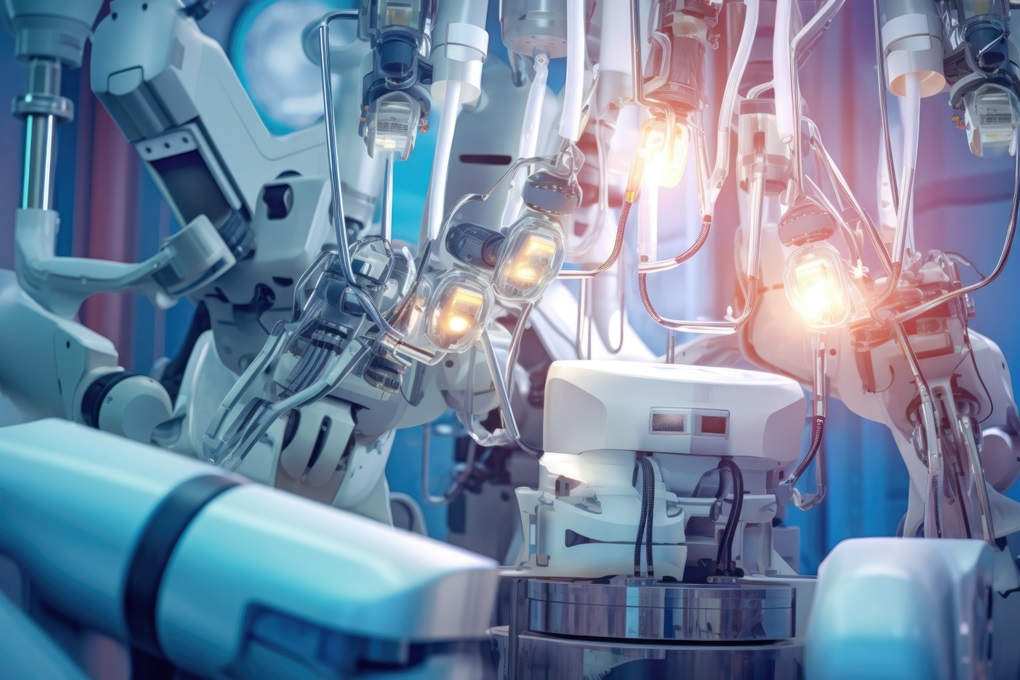

Pierwsze operacje ginekologiczne robotem da Vinci